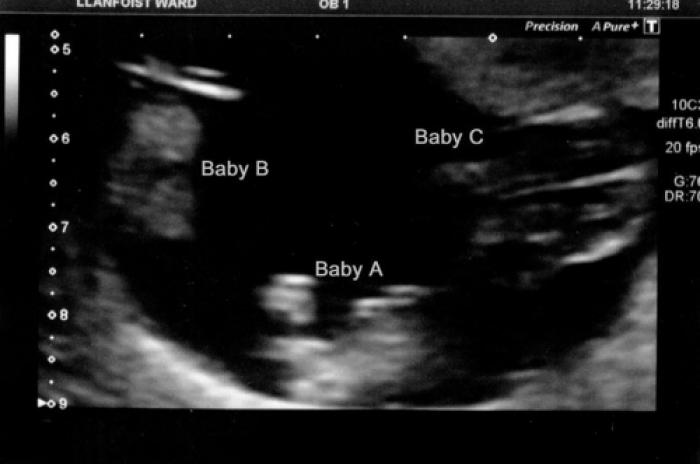

Șansele erau de una la 200 MILIOANE! Ce a descoperit o femeie însărcinată la ecografie

Ashley Alexander, o femeie din SUA a adus pe lume trei gemene identice, un caz extrem de rar care i-a uimit pe medicii care au supravegheat sarcina.